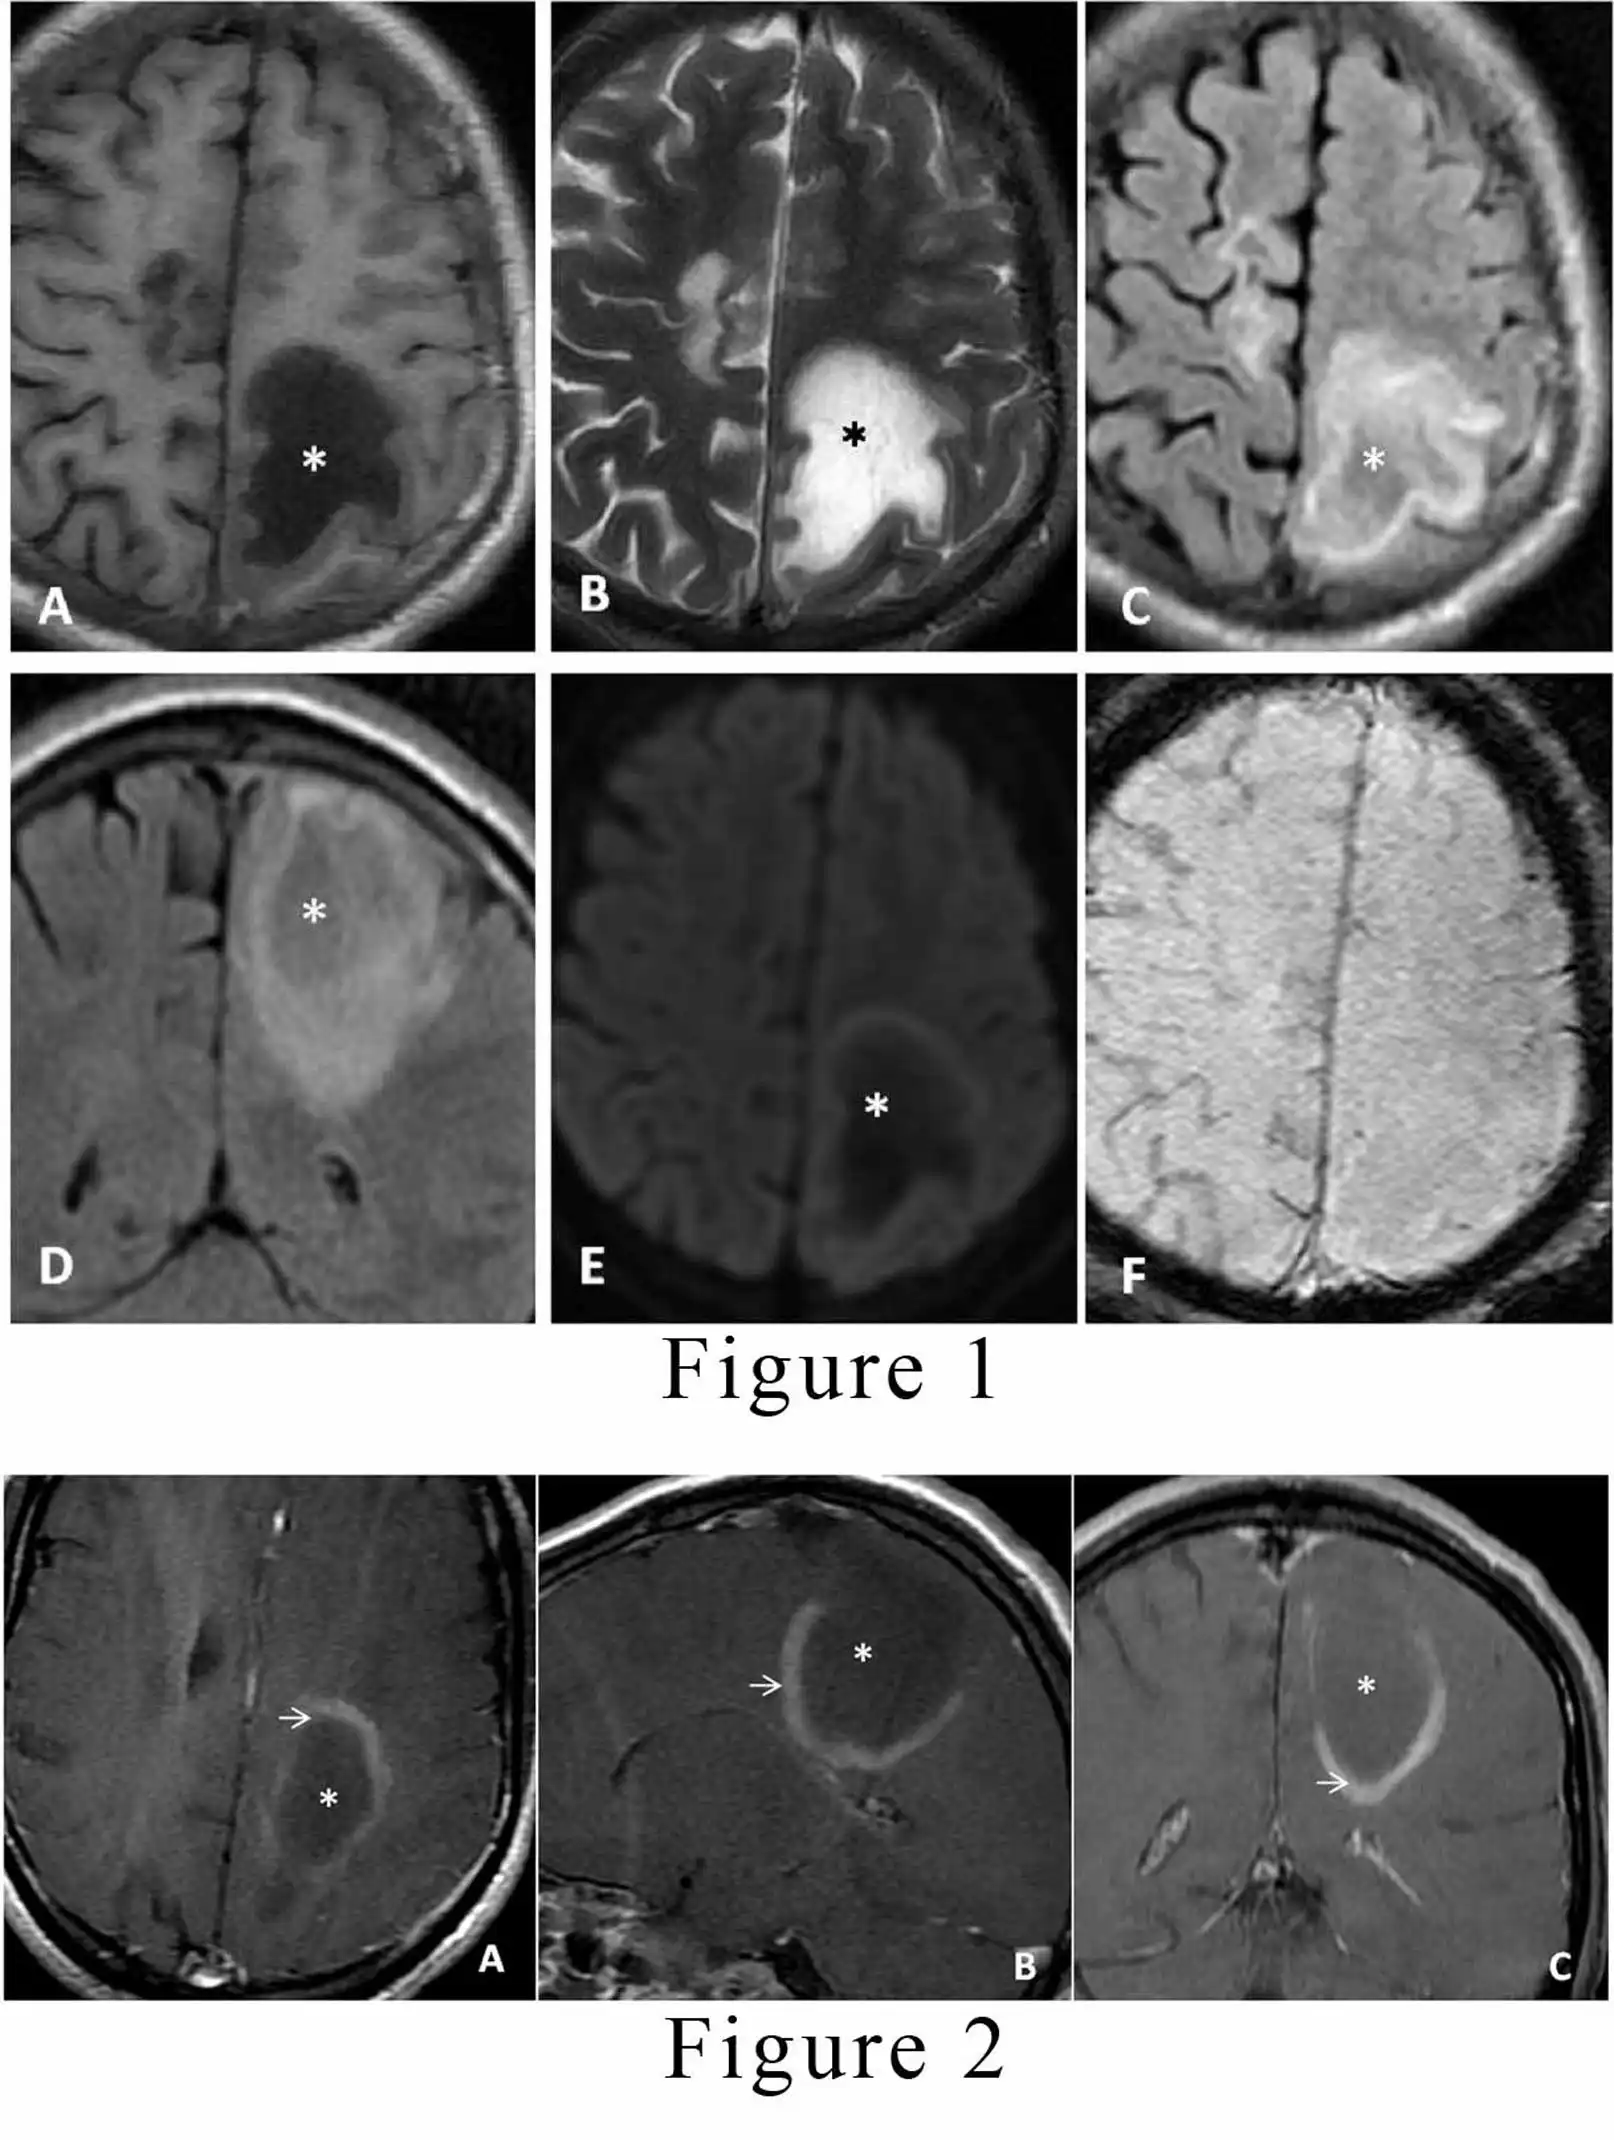

Tumefactive demyelinating lesions (TDLs) are large lesions, usually greater than 2 cm. They typically occur as a solitary lesion or as few separate lesions. [1,2] There is a slight predominance in women with a mean age of 37 years. These lesions usually do not originate as post-infectious or post-vaccination status and do not progress to multiple sclerosis.[1] The patient usually presents with focal neurological deficit, aphasia or seizures. There is typical involvement of supratentorial white matter sometimes extending to involve cortical gray matter. On contrast-enhanced magnetic resonance imaging (MRI), there is an open ring type of enhancement.[2,3] The incomplete portion of the ring is on the gray matter side of the lesion. The enhancing part of the ring represents the acute demyelinating process, whereas the non-enhancing part represents the chronic phase of the inflammatory phase.  A 42-year male presented to our institute with a history of blurred vision, paresthesia and motor weakness on right side since one month. There was no history of any similar episode, vaccination or respiratory tract infection. He had a 2/6 vision in the right eye with a normal B-scan and fundal examination on ophthalmic evaluation. The routine blood and serological investigations were unremarkable. For further evaluation, he was advised an MRI scan of the brain, which revealed two abnormal intensity lesions in bilateral frontoparietal lobes; the right-sided lesion measured 27 x 9 mm, and the left lesion measured 52 x 25 mm. The lesions were hypointense on the T1 weighted image, and predominantly hyperintense on both T2 and FLAIR weighted images.[Figure 1A, 1B, 1C, and 1D] There was only minimal surrounding oedema present without any significant mass effect over the adjacent brain. No diffusion restriction or blooming was observed in the lesions on diffusion-weighted images and susceptibility-weighted images, respectively.[Figure 1E, and 1F] The suspicion of glioma and demyelinating disease was raised on the basis of a non- enhanced MRI. For further analysis, contrast-enhanced MRI was advised. On post-contrast sequence, the lesions demonstrated peripheral arc-like enhancement giving a characteristic open/incomplete ring appearance.[Figure 2A, 2B, and 2C] The diagnosis of tumefactive demyelination was made based on clinical history and MRI features. The patient was started on standard steroid treatment, and the patient recovered completely from his visual symptoms and paresis. Presently he is on follow up with our hospital and is doing fine.

• Figure 1. Unenhanced magnetic resonance imaging (MRI) brain (A, B, C, and D) axial T1 weighted imaging (T1WI), T2WI, Fluid attenuation inversion recovery sequences (FLAIR), and coronal plane FLAIR respectively; demonstrate an irregular abnormal signal intensity lesion with perilesional edema (asterisk) following fluid signals involving left high parietal region predominantly involving white matter. Figure 1 (A, B, and C) axial images shows similar lesionin right fronto-parietal region. (E and F, axial planes) The lesion in left parietal region does not demonstrate diffusion restriction or blooming on diffusion-weighted imaging (DWI) and susceptibility-weighted imaging (SWI) respectively.

• Figure 2. T1WI, contrast-enhanced MRI (A, B, and C) axial, sagittal, and coronal planes respectively; demonstrate peripheral incomplete ring enhancement (white arrow) with the non-enhancing central area (asterisk) of the lesion. Open portion of the ring enhancemnet is on gray matter side.